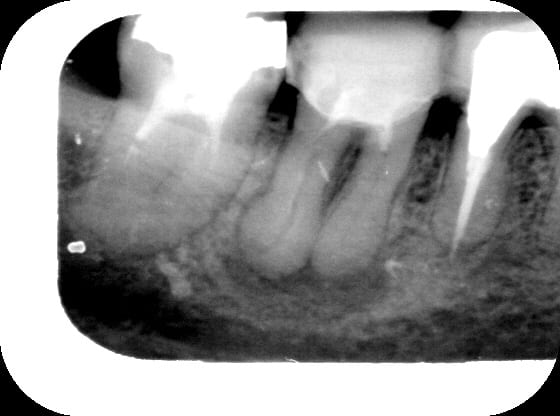

alors là.... rep endo pas simple mais sans soucis... sf que entre la radio pre et post reprise, il y a comme qui dirait un passage de pate par une perfo du plancher....mais j'ai pas vu de perf du plancher....

bref...vous pensez que c' est quoi? une perf obturée? un ttt endo du desmodonte? ...

moi qui n'ai jamais osé lancer le debat du petit dépassement de pâte en cas de lésion apicale (peut être déjà traité d'ailleurs?), je suis totalement rassurée...pour ce qui est du desmodonte, ça ressemble quand même bien à une perfo, le plancher avait l'air très fin sur la radio préop..?

une remontée de pate peut etre....attends une radio a distance et tu verras la pate se dissocier et t'eclairer un peu...

si tu es sûre qu'il n'y a pas de perfo, ne serait-ce pas une "remontée" de pâte par l'apex? C'est certes volumineux mais on ne sait jamais

Je crois pas trop a la perf, tu aurais pas un tracé comme ça. De toute façon c'est RX a 3 semaines puis à 1 mois puis a 3 mois et soit les peches se barrent soit, de toute façon..

ce qui m'interpelle,n'est finalt pas la cause mais les conéquences

si pareille remontée de pâte cela signifie que au niveau osseux l'espace interadiculaire est lésé,non?

tu a sondé?

c'est un cas ou je serai tenté d'aller voir en faisant un lambeau(à 3 semaines ,1 mois si pas mieux) et eventuellement de faire séparation de racines et 2 couronnes soudées avec embrasure haute pr passer brossetteinterdentaire?

Il peut y avoir de tres petites communications au niveau du plancher. Alors pourquoi pas un de ces "canaux" qui donnent passage a la pate lors de l'obturation.

En effet, d'accord avec ce qui a été dit : si tu avais eu une perf du plancher, la pâte serait resté très localisée sous celui-ci. Là, la pâte a sans doute suivi un trajet de fistulisation.

Par contre, je ne ferais pas de lambeau d'exploration (pourquoi faire ?), j'attendrai simplement avec un inlay core + prov pendant 6 mois voir, 1 an.

Comme Athos ou Gai-luron, ça me fait aussi penser à une remontée de pâte dans une voie de fistulisation.

Dans l'immédiat, wait and see...

bref...depuis, Mme X est revenu, elle avait eu un peu mal après la reprise d'endo faite sans anesth locale, et voici la rx du jour....

Comme quoi, du moment que c'est "propre", un dépassement n'empêche pas la cicatrisation...